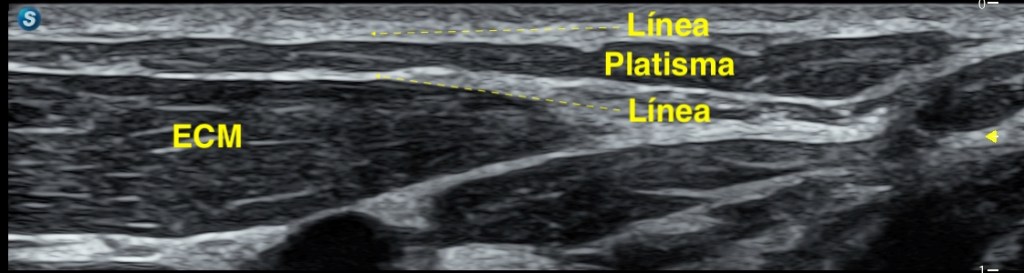

El Platisma es un músculo superficial, plano y muy fino, situado justo por debajo de la piel y del tejido celular subcutáneo, es el músculo más superficial del cuello.

Por encima de él solo encontramos piel y grasa, tejido celular subcutáneo en más o menos medida. Por debajo, ya entramos en estructuras más profundas del cuello anterior.

Te presento al músculo, en una imagen, como mejor puedo hacerlo, luego vamos a ir viendo sus relaciones anatómicas.

Por eso, el Platisma tiene una importancia clave: Marca el límite entre lo superficial y lo profundo en el cuello.

Una vez optimizada la técnica, el platisma se reconoce como una estructura muy fina, hipoecogénica, de aspecto plano y continuo, sin un patrón fibrilar tan evidente como el de otros músculos, repito muy variable en su presentación. Se localiza entre la grasa subcutánea, que es más ecogénica, y los planos musculares profundos, que presentan una arquitectura más definida. Podemos identificarlo como entre dos laminas hiperecogénicas. Como un bocadillo. El ECM siempre nos va a ayudar, un buen libro de anatomía del cuello al lado, tambien.